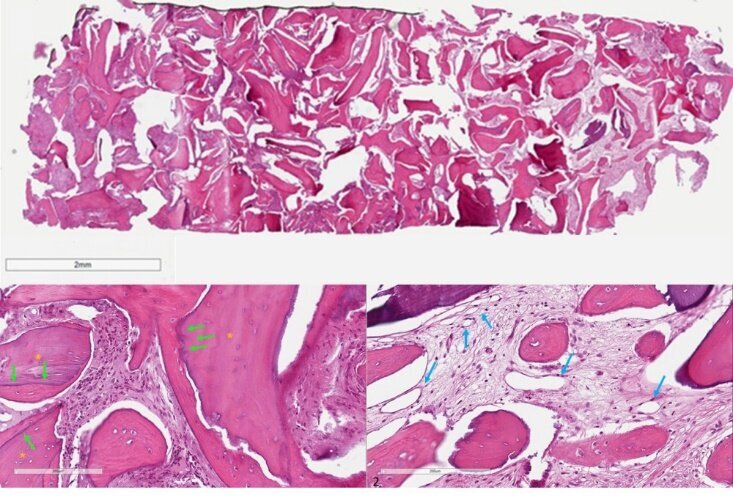

Il campione bioptico è stato decalcificato, incluso in paraffina e ne sono state ricavate delle sezioni sottili (3 μm), montate su vetrino e colorate con ematossilina/eosina. Dopo digitalizzazione del vetrino mediante uno scanner dedicato (Aperio Scanscope, Leica, Milano), le immagini sono state analizzate per fornire una valutazione istologica generale (strutture tessutali e cellulari visibili) e una misura istomorfometrica della quantità di osso vitale, di biomateriale residuo e di altro tessuto presenti nella sezione considerata. La biopsia è stata processata ed analizzata dal Laboratorio di Sezioni Sottili, Dipartimento DISBIOC, Università degli Studi di Milano, Italia.

Non si sono osservate complicanze intra- o post-operatorie. A distanza di 6 mesi dall’inserimento implantare la protesi è funzionante (Fig. 7) e non si osserva riassorbimento osseo perimplantare (Fig. 8). Il quadro istologico (Fig. 9) mostra granuli di biomateriale che appaiono inglobati da tessuto osseo neoformato e ben osteointegrati nella matrice calcificata. Le aree di interfaccia tra osso ed innesto appaiono ben in contatto senza evidenza di gap. La matrice calcificata mostra diversi gradi di mineralizzazione. Gli spazi midollari sono caratterizzati dalla presenza di numerosi vasi sanguigni. Nella porzione più coronale del campione si evidenzia la presenza di un infiltrato infiammatorio. Nel complesso, il tessuto appare vitale, ben vascolarizzato e in una fase del rimodellamento osseo fortemente spostato verso la fase anabolica caratterizzata dalla deposizione di nuova matrice rispetto al riassorbimento delle particelle innestate. La quantità di osso di nuova formazione raggiungeva in alcune sezioni del campione il 43.8% (Tabella 1).

Tabella 1 - Risultati dell’analisi istomorfometrica. A, B, C: sezioni del campione bioptico prelevato a 6 mesi dall’intervento rigenerativo. Il tessuto osseo di nuova formazione si suddivide in osso e tessuto osteoide.

Fig. 9 - Analisi istologica. Le sezioni ossee complete (in alto) appaiono composte di tessuto osseo di nuova formazione, compreso tessuto di tipo osteoide, nonché di particelle biomateriale residuo. L’analisi a maggiore ingrandimento mostra (sinistra) granuli di biomateriale (asterischi gialli) inglobati da tessuto osseo neoformato ben osteointegrati nella matrice calcificata, con cui sono in contatto senza evidenza di gap (frecce verdi). Gli spazi midollari (destra) sono caratterizzati dalla presenza di numerosi vasi sanguigni (frecce blu).